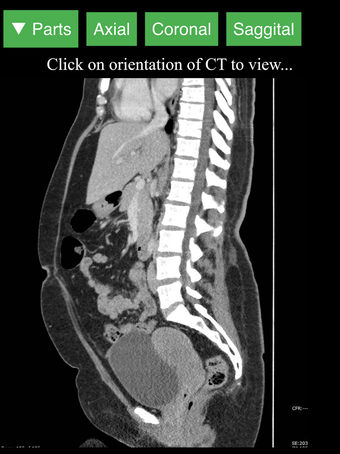

Radiology CT Viewer - полезный инструмент для врачей, медицинских студентов, радиологических техников и других медицинских специалистов, которые хотят узнать больше о человеческом теле и его анатомии. Приложение содержит подробные сечения наиболее важных частей тела. Кроме того, оно содержит интерактивную 3D-модель, которая позволяет вращать, увеличивать и перемещать камеру вокруг изображения, чтобы получить лучший обзор анатомии.

Если вы ищете инструмент, который поможет вам узнать больше о человеческом теле, Radiology CT Viewer - отличный выбор. Он содержит подробные иллюстрации и интерактивную 3D-модель.